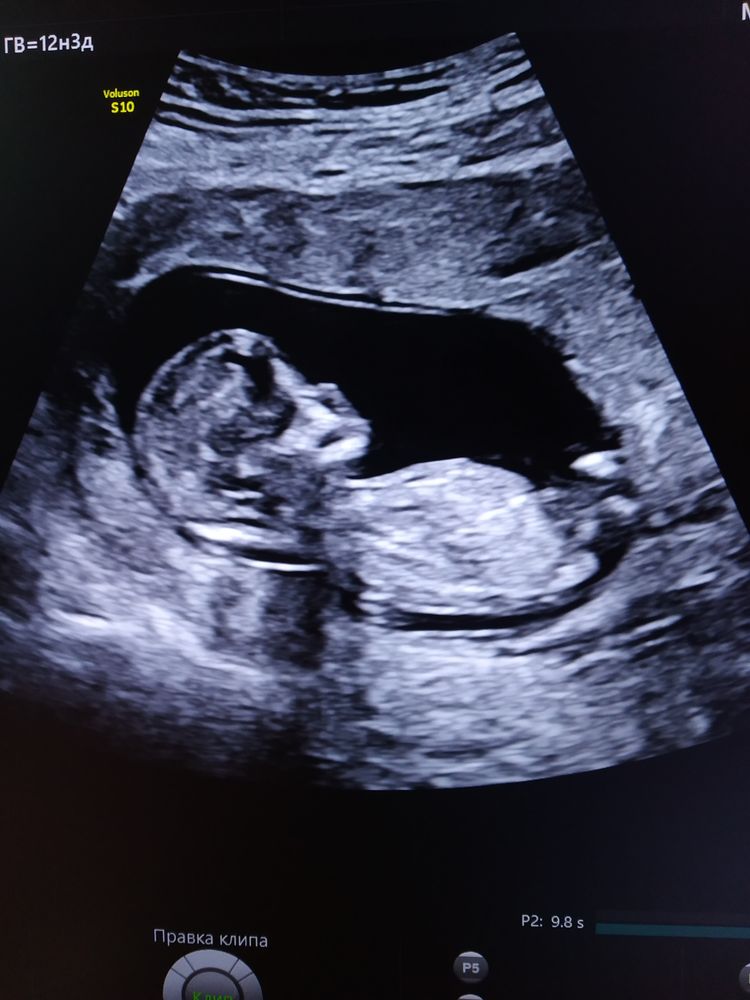

Начался второй триместр, стала чувствовать себя легче, слабость, сонливость ушли, токсикоза у меня и не было. На этой неделе пришёл результат НИПТ, делали по совету врача после плохой биохимии крови в Отта на Васильевском острове. УЗИ было хорошим, а вот кровь не очень, бетаХГЧ повышен в три раза, а белок, наоборот, понижен. Результат НИПТ оказался хорошим, низкие риски, пол - женский😍 Муж, конечно, хотел мальчика, но он рад. Наблюдаюсь у М.И. Ярмолинской в Отта и стою на учёте в своей ЖК.